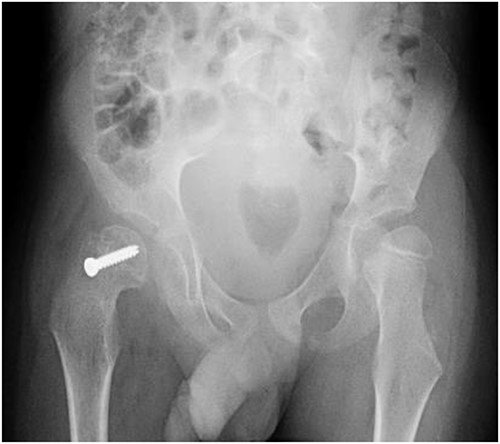

A 5-year-old independent ambulatory Middle Eastern boy with CP who was born preterm and developed grade III intraventricular haemorrhage and periventricular leucomalacia and was on AEDs, including valproic acid (VPA) and levetiracetam (LEV), for >3 years and was controlled over the last year (no history of seizure attack) presented to the emergency room (ER) with right hip pain and inability to bear weight for 4 weeks; the patient had no history of fever or trauma. Physical examination shows a thin, the weight is 12 kg, the height is 101 cm, vital signs within the normal range, tenderness over the right hip, and external rotation of the right hip, with restricted hip mobility. A radiological study was performed ~3 months before the patient presented to the ER for follow-up examination of a left hip coxa valgus deformity with no apparent abnormalities in the right hip (Fig. 1). Initial imaging studies conducted in the ER showed an anterior–posterior view of the pelvic radiograph, revealing Klein’s line [13] not intersecting the capital femoral epiphysis (Fig. 2), and frog-leg lateral view radiograph of the right hip (Fig. 3) confirmed SCFE and Southwick’s slip angle [13] of ~50° (moderate). Laboratory findings were clear for endocrine and renal diseases or infection, except for low vitamin D (total 25-OH Vitamin D: 43.4 nmol/L), suggesting vitamin D insufficiency. The diagnosis was confirmed with clinical and radiological studies as right-sided unstable SCFE requiring surgery. Surgical intervention was performed with percutaneous in situ fixation using a single fully threaded 4.5-mm cannulated screw (Fig. 4). Postsurgical rehabilitation included non-weight-bearing right lower extremities for 6 weeks. Regular follow-up with serial radiology studies showed stable fixation with no migration of screw or further slippage at 6 weeks (Fig. 5) and 3 (Fig. 6), 15 (Fig. 7), and 36 months (Fig. 8). During follow-up, a painless range of motion in the right hip was observed, with full weight-bearing and resumption of his usual activities with no complaints.

Pelvic anterior–posterior radiograph immediately after in situ fixation with single cannulate screw.